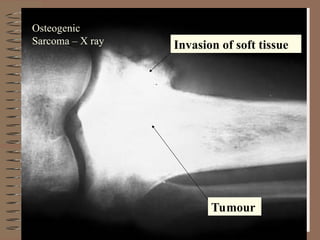

Tumour Invasion of softtissue Osteogenic Sarcoma – X ray

Tumour

Invasion of soft tissue

Osteogenic

Sarcoma – X ray

X ray –The tumour elevates the perostium to form cod man triangle formed by the angle between the elevated periosteum and the surface of the involved bone . Sunburst pattern due to osteogenesis within the tumour may also occur Parosteal (Juxta cortical ) osteosarcoma arise from the external surface of the bone ( parosteal or juxta cortical means outer to the cortex ) This has better prognosis